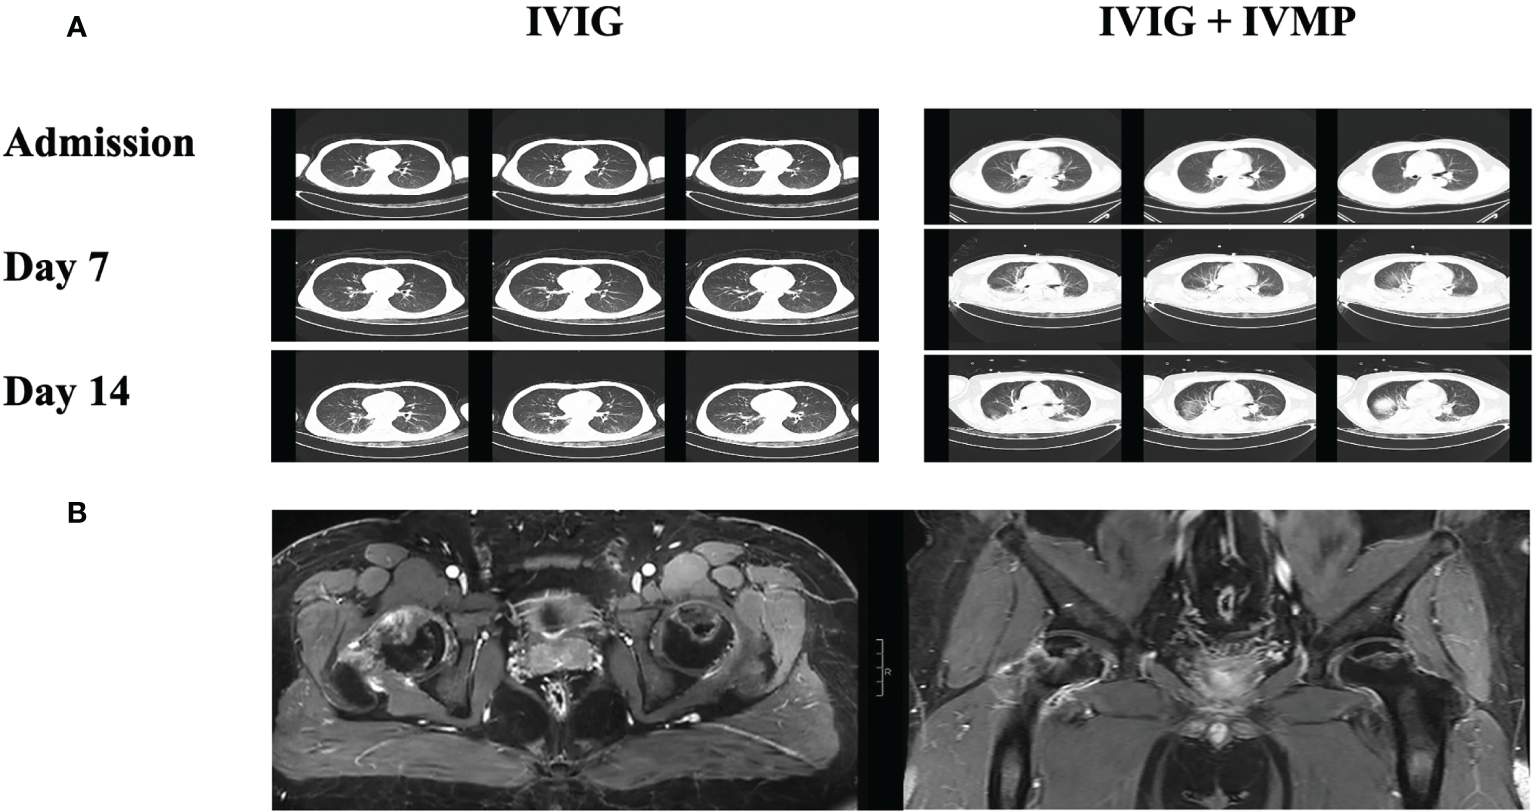

Abnormalities in Lung CT or Chest X-ray were found to be more in IVIG + IVMP group (60% vs 35.71%, P < 0.001). Images of chest CT scan evolution of cases in two groups during treatment were showed in Figure 2A. No significant difference in median body temperature was observed between the two groups within 5 days after first-line immunotherapy (P = 0.098). However, the duration of fever was shorter in the IVIG + IVMP group than in the IVIG group, even though there was no significant difference [7 vs. 4; P = 0.26].

FIGURE 2

www.frontiersin.org

Figure 2 Images of chest CT scan evolution of cases in two groups during treatment and images of steroid-induced necrosis. (A) Images of chest CT scan at admission, 7 and 14 days after immunotherapy from cases in IVIG groups and IVIG + IVMP group. (B) Images of MRI scan of steroid-induced necrosis from case in IVIG + IVMP group.

3.3 Comparison of Noninfectious Complications and Outcomes of Anti-NMDAR Encephalitis

Of the 244 patients, 174 (71.31%) had at least one noninfectious complication, including deep venous thrombosis/pulmonary embolism (DVT/PE), gastric stress ulcers, electrolyte disorders, abnormal liver function, abnormal kidney function, hypoalbuminemia, multiple organ dysfunction syndrome (MODS), respiratory failure, steroid-induced necrosis of the femoral head, and other complications (Figure 1B). Patients in the IVIG + IVMP group had a significantly higher number of complications than those in the IVIG group (76.25% vs 61.90%, P = 0.018; Figure 1B). The proportions of DVT/PE, gastric stress ulcers, electrolyte disorders and abnormal liver function were significantly higher in the IVIG + IVMP group (8.75% vs 1.19%, P = 0.039; 15.63% vs 4.76%, P = 0.022; 32.50% vs 14.29%, P = 0.004; 21.88% vs 10.71%, P = 0.024, respectively; Figure 1D). Images of MRI scan of steroid-induced necrosis from case in IVIG + IVMP group were showed in Figure 2B.